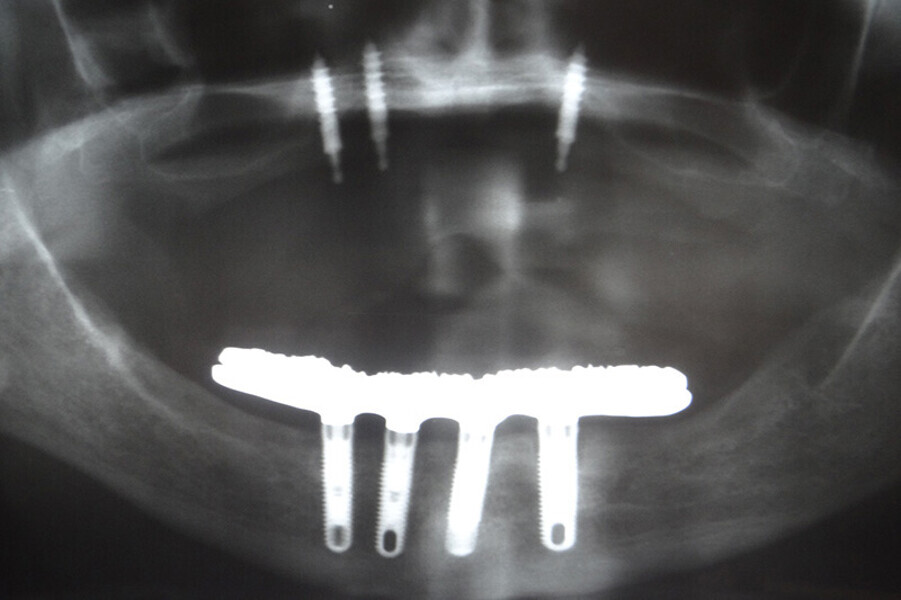

Fig. 6. Prótesis Híbrida inmediata y radiografía control con 6 años post-operatorio